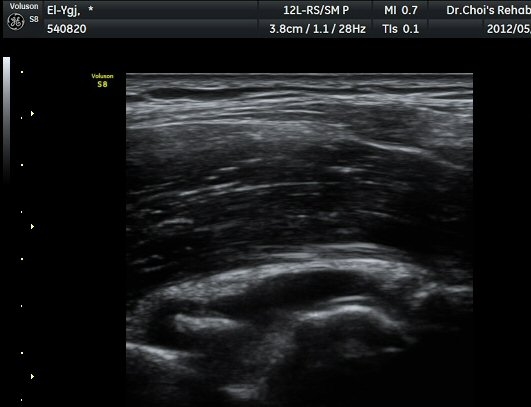

ÆÈ²ÞÄ¡ ¿ÜÃø Á¾´Ü¸é°Ë»ç¿¡¼­ ¼ÒµÎ ¾ÕÂÊ¿¡ ¼ö¾×Àú·ù°¡ °üÂûµÈ´Ù(±×¸² 1).